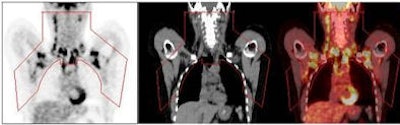

The PET/CT scans identified substantial areas of brown adipose tissue from the anterior neck to the thorax. Positive scans were seen in 76 of 1,013 women (7.5%), compared with 30 of 959 men (3.1%). Women also had a greater mass of brown adipose tissue and higher FDG uptake activity.

| Brown adipose tissue (BAT) volume and activity can be quantified in a "fat map." Regions of interest (red outline) include the principal cervical, supraclavicular, and superior mediastinal BAT depots, from left to right, in the PET, CT, and fused PET/CT images. Image courtesy of Dr. Aaron Cypess, Joslin Diabetes Center. |

The PET/CT scan of the 67-year-old woman showed a tumor with the density of brown fat, but with greater than typical FDG uptake for subcutaneous or visceral fat depots. "PET tells us where the very highly metabolic tissue is," he added. "In our study, we saw a percentage of the people studied had brown fat you could see, with the likelihood that more people have it."